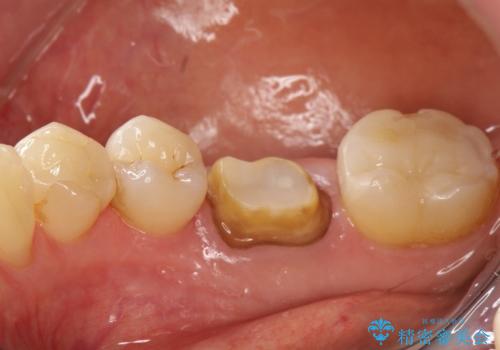

咬んだ時の違和感 顕微鏡で発見された歯の穴を処置し、かみ合わせを回復する

- 再根管治療にて発見されたパーフォレーションを修復し、改めてかぶせ物を製作する。

レントゲンに大きな問題がなくても、実際に顕微鏡で見ることにより様々な問題が露呈することはよくあります。

再治療の繰り返しにより歯に穴があいてしまっていることもよくありますが、このような深い位置の穴は、特殊なセメントで封鎖することにより非常に経過良く処置することができます。